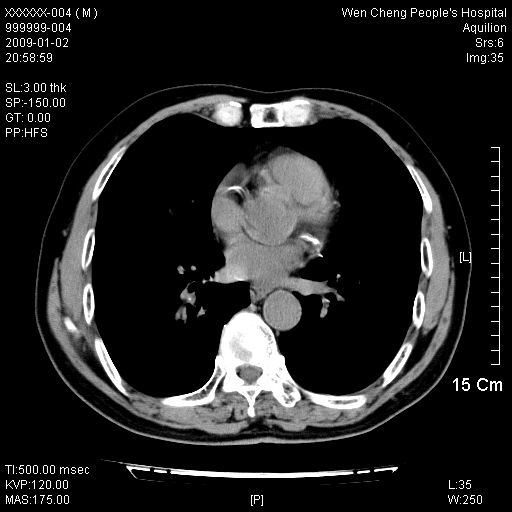

男性,73岁,有慢支病史,肿瘤系列标志物检验正常,血沉及血常规正常

右肺下叶背段小片状 磨玻璃样模糊影,内见血管及含气支气管像,支气管管壁增厚。考虑:慢性炎症!

1)不排除右肺下叶周围型肺癌可能;建议追踪复查。2)左右冠状动脉钙化。

右肺下叶背段小片状 实性与磨玻璃样影,内见血管及含气支气管像,支气管管壁增厚,边缘见长毛刺影。考虑:慢性炎症或肿瘤!建议抗炎治疗复查,密切观察随访!

右肺下叶片团状影内见扩张的含气支气管和支气管管壁增厚,其周有磨玻璃样模糊影和长毛刺。考虑慢性炎症可能性大。

2、右肺下叶片团状影内见扩张的含气支气管和支气管管壁增厚,其周有磨玻璃样模糊影和长毛刺。考虑周围型肺ca可能,结核不排。

高度提示细支气管肺泡癌,建议抗炎治疗半月观察病灶变化,如无明显改变,建议立即手术治疗.

病变形态非常不好呀,临床上血常规及症状也不明显,不太支持炎性病灶,高度警惕肿瘤病变,最好做个纤支镜检查。